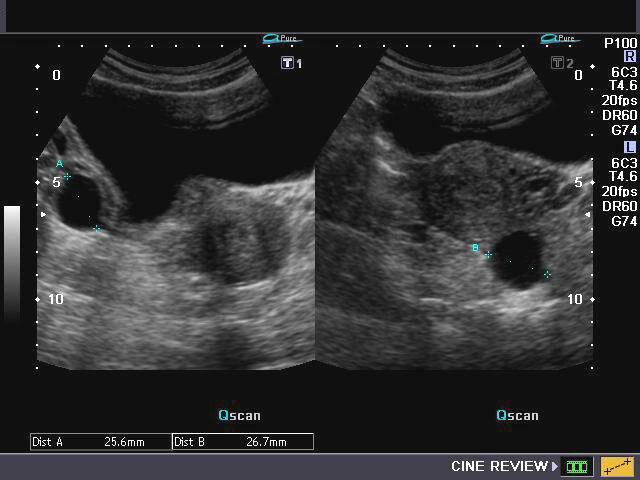

- УЗИ органов малого таза — основной и обязательный метод исследования — выдает информацию о размерах, формах, структуре, месте расположения опухоли;

- УЗИ влагалища (трансвагинальная эхография) позволяет получить более конкретную информацию о происхождении (доброкачественная или злокачественная) опухоли по специальной шкале;

Самый доступный и достоверный метод исследования – УЗИ, с его помощью можно отследить положение, размеры, динамику развития.

- Фолликулярная киста, которая развивается в одном яичнике и чаще встречается у женщин молодого возраста. Диаметр ее составляет от 2,5 до 10 см. Она подвижна, эластична, может быть расположена над маткой, позади или сбоку от нее, не склонна к злокачественному перерождению. Киста проявляется нарушениями менструальных циклов в виде задержки менструаций с последующими обильными кровотечениями, однако после нескольких (3-6) менструальных циклов она самостоятельно исчезает. Тем не менее, возможен перекрут ножки опухоли яичника, в связи с чем при ее обнаружении во время УЗ исследования необходимо постоянное наблюдение с проведением УЗ биометрических измерений до ее исчезновения.

- Киста желтого тела. При пальпации (мануальное прощупывание) живота она имеет сходство с предыдущей. Ее размер в диаметре колеблется в пределах 3-6,5 см. В зависимости от вариантов опухоли, при проведении УЗИ могут определяться однородная структура, наличие единичных или множественных перегородок в кисте, различной плотности сетчатые пристеночные структуры, сгустки крови (предположительно). Симптоматически киста характеризуется задержкой менструаций, скудными кровяными выделениями из половых путей, нагрубанием молочных желез и другими сомнительными признаками беременности. Поэтому необходимо проведение дифференциальной диагностики кисты желтого тела с эктопической беременностью. Возможен разрыв кисты, особенно при половом акте.

- Серозная, или простая киста. До проведения гистологического исследования ее часто принимают за фолликулярную. Предполагается возможность малигнизации (озлокачествление) серозной кисты, что окончательно не доказано. Киста развивается из остатков первичной зародышевой почки и представляет собой подвижное плотноэластичное образование диаметром около 10 см, но иногда, хотя и очень редко, может достигать значительных размеров. Опухоль чаще обнаруживается в результате перекрута ее ножки или во время проведения УЗИ по другому поводу. При этом рядом с новообразованием хорошо просматривается ткань яичника.